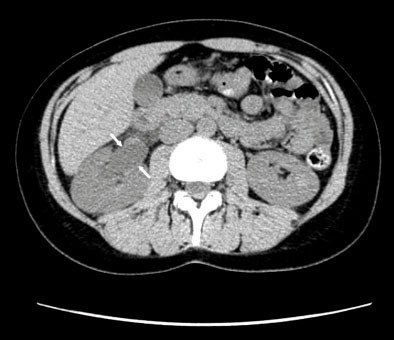

Vladimir Gomola, Jacques Hubert (La Revue du Praticien) Tomodensitométrie non injectée en coupe axiale mettant en évidence une dilatation du pyélon droit.